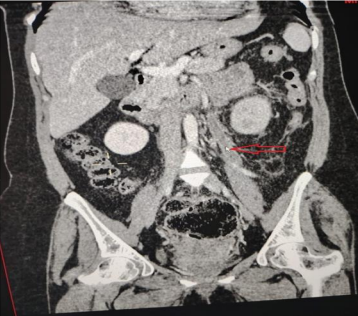

Laboratory exams revealed elevated white blood cell (WBC) count (12000 cells/mm3) with neutrophilia and (20-25 WBC in high power field) in urine examination. Other inflammatory markers like c-reactive protein (CRP) and erythrocyte sedimentation rate were also high. The initial differential diagnosis was cystitis or pyelonephritis. Abdominal ultrasound showed an enlarged left kidney, no hydronephrosis and no stones. A urine sample was sent for culture and sensitivity. The patient was admitted, and antibiotics and painkillers were initiated. An abdominal and pelvic computed tomography (CT) scan was arranged to be done the next day. CT scan with contrast showed left OVT (Figure 1, Figure 2) extending to the left renal vein (Figure 3) and inferior vena cava. Thus, she was started on anticoagulants. Urine culture was positive for Escherichia coli (ESPLs). She received low molecular weight heparin (LMWH) and shifted to warfarin. The patient was discharged home after 1 week on warfarin & oral antibiotics. A follow-up CT scan after 3 months, revealed the resolution of the clot.

Figure 2: Coronal view, contrast-enhanced CT scan demonstrates distended thrombosed left ovarian vein (red arrow)